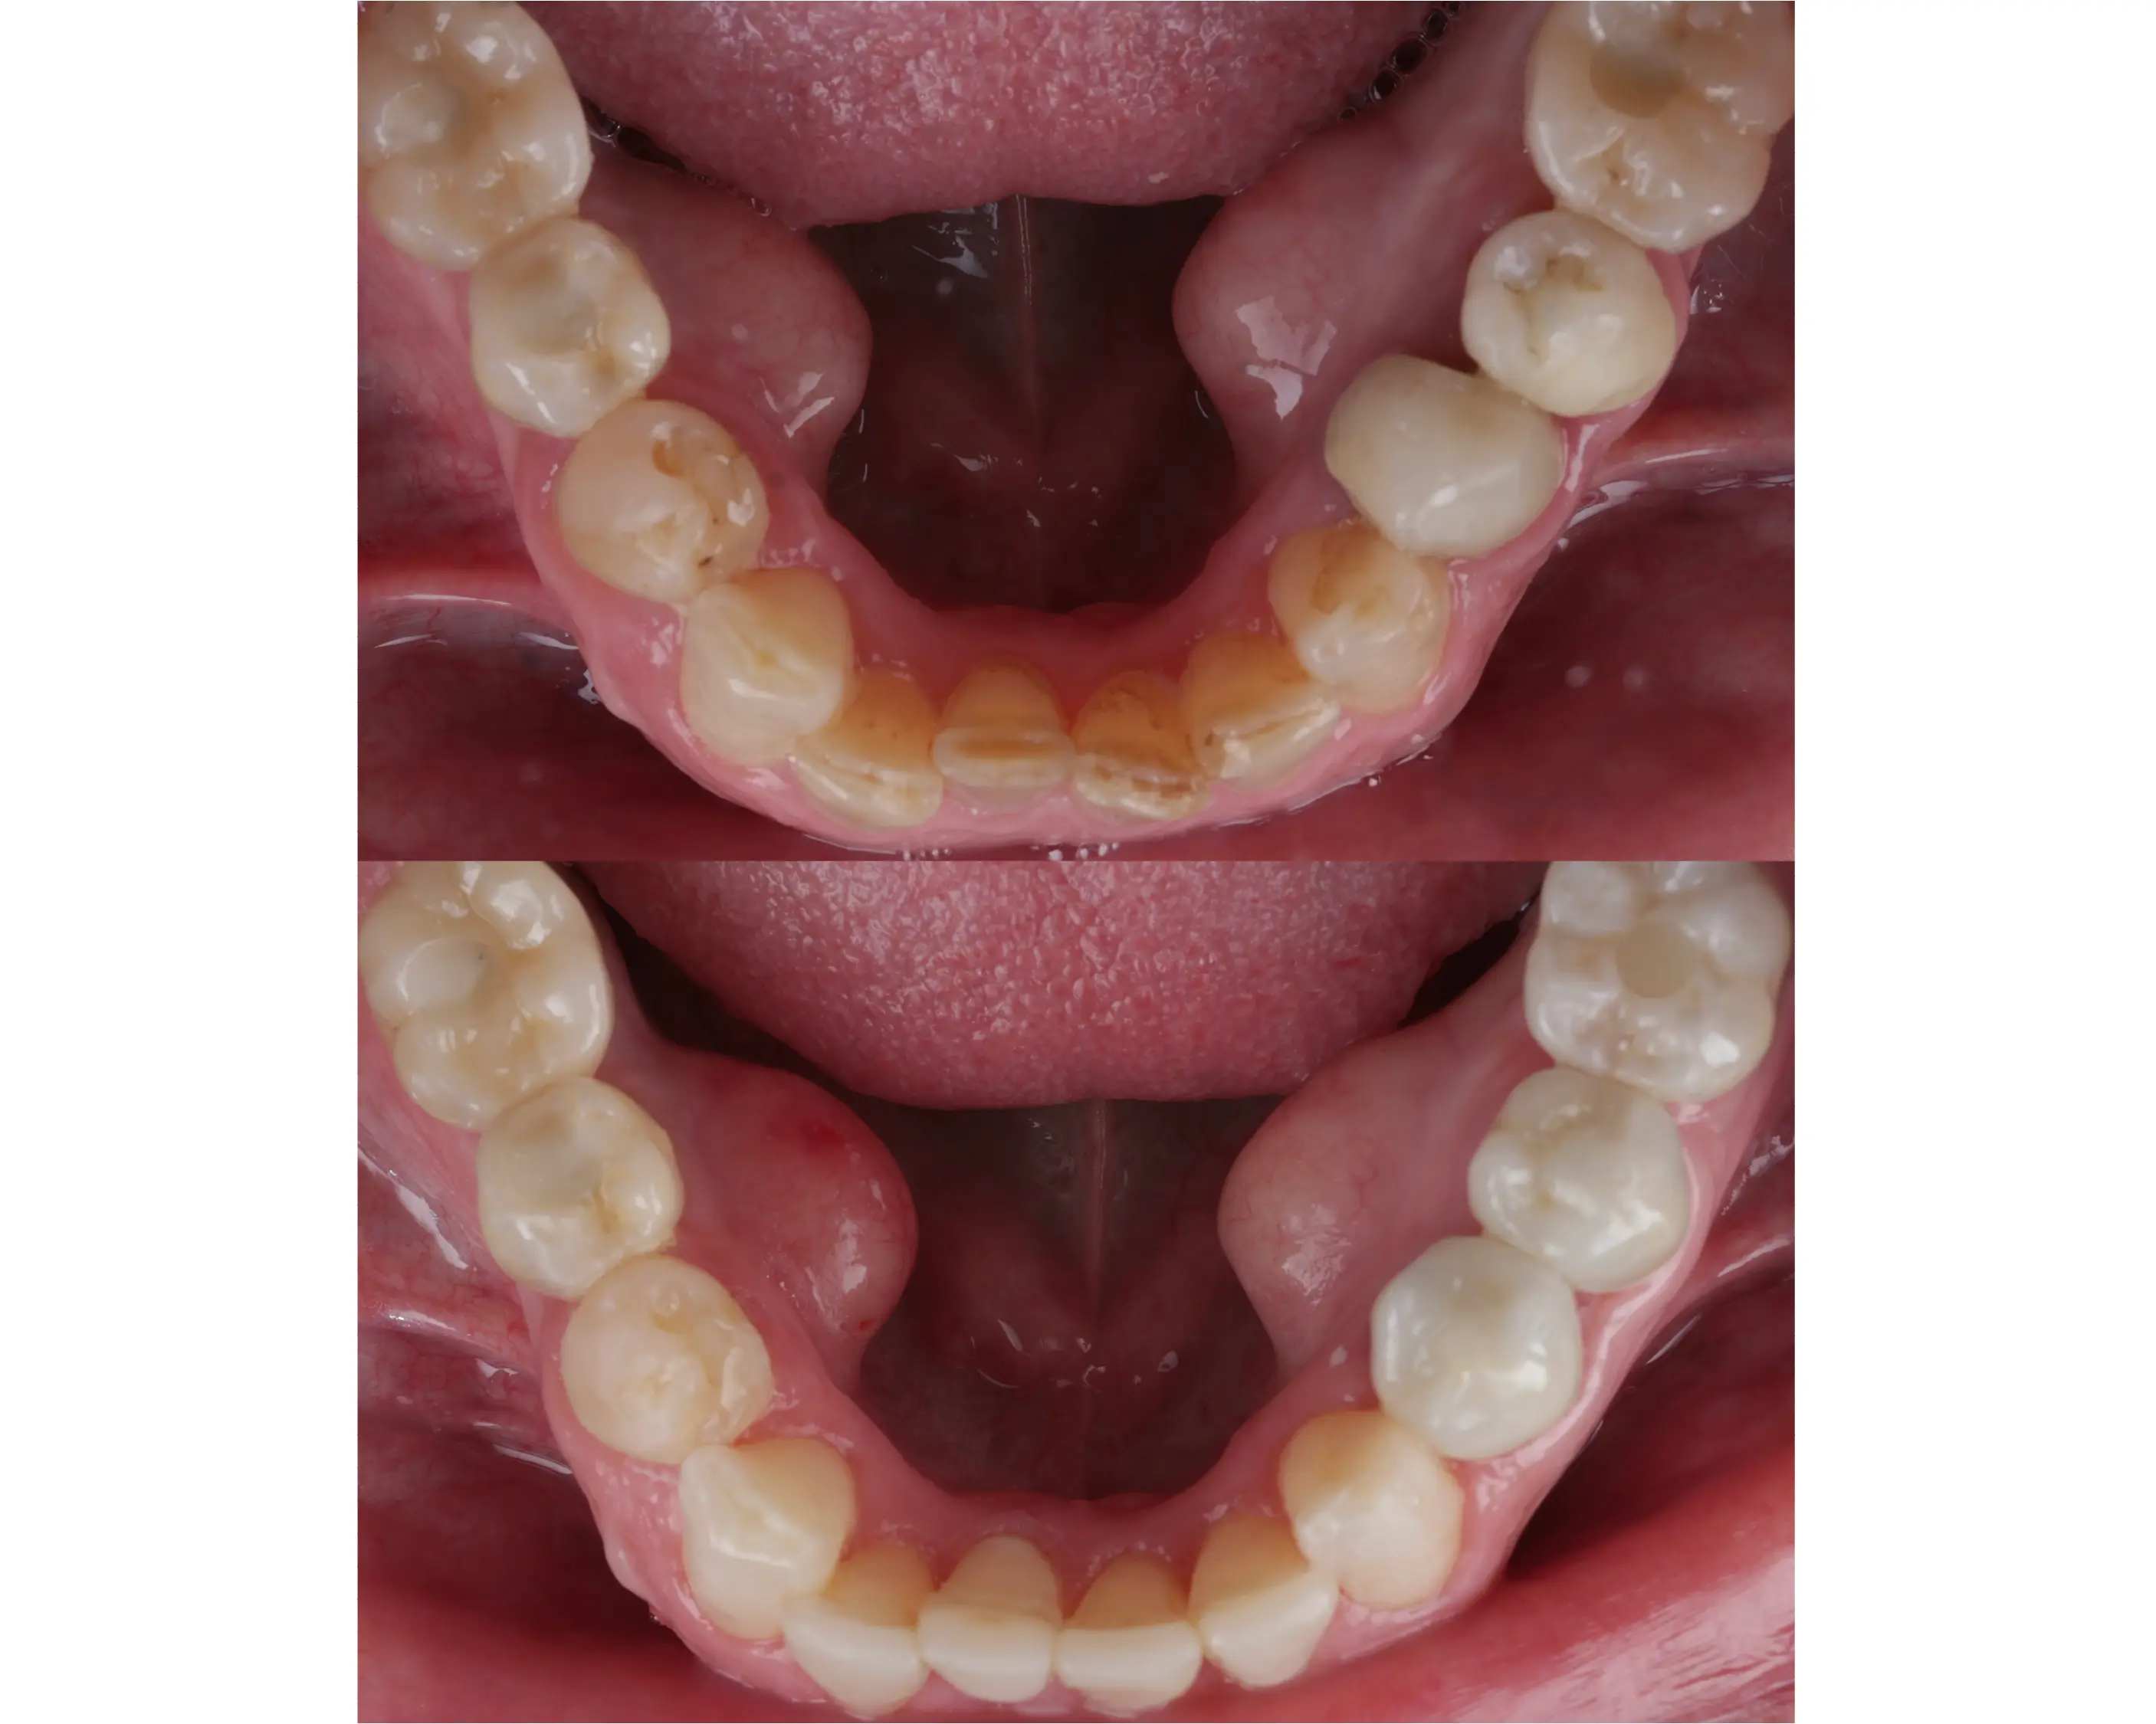

Denne 57-årige kvinde kom til os med et ønske om et smukkere smil og en mere velfungerende tyggeevne, da hun manglede flere tænder i overkæben. For at skabe balance og funktion blev biddet hævet med en kombination af plast og porcelæn. Derudover har vi lavet broer på implantater i begge sider af overkæben samt tre nye kroner i underkæben. Resultatet er et naturligt og harmonisk smil – og en markant forbedret tyggefunktion, der gør hverdagen lettere og mere behagelig.